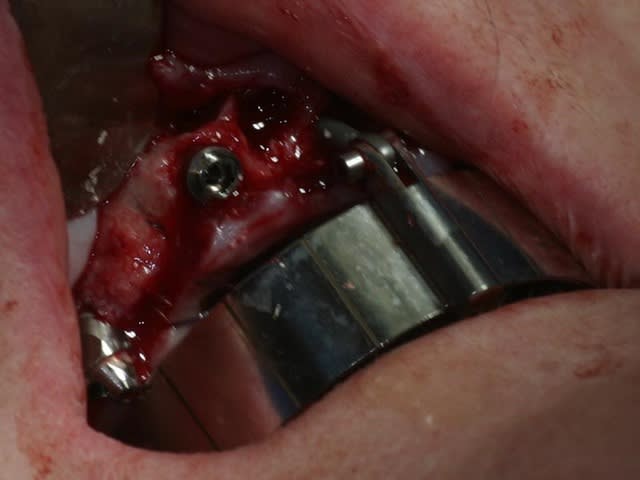

bon, toujours aussi speed je suis, mais après certaines réclamations, et malgrès ma réticence à poser un cas non "consolidé", voici en avant première mon premier all on 4, version photos ratées et non retouchées, mais... speed je suis je vous disais ;)

sto le bla bla, et pasons le diaporama... bon voyage au pays de la mise en charge immédiate totale au maxillaire de fille carole sur dame ginette, une patiente en or que j' adore, et pour qui je suis très très heureuse d' avoir pu réaliser cette chirurgie et la première étape prothétique.....

Tu as utilisé des Nobel Speedy si je ne me trompe pas.

Peux tu nous en dire un peu plus sur les implants, leurs diamétres et leur longueurs ?

du 4 par 15 ?